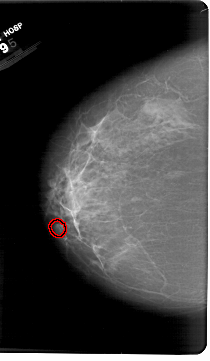

A_1386_1.LEFT_MLO

LEFT_MLO LINES 6421 PIXELS_PER_LINE 4351 BITS_PER_PIXEL 12 RESOLUTION 43.5 OVERLAY

FILE: A_1386_1.LEFT_MLO.OVERLAY

TOTAL_ABNORMALITIES 1

ABNORMALITY 1

LESION_TYPE CALCIFICATION TYPE AMORPHOUS DISTRIBUTION LINEAR

ASSESSMENT 4

SUBTLETY 1

PATHOLOGY BENIGN

TOTAL_OUTLINES 1

BOUNDARY